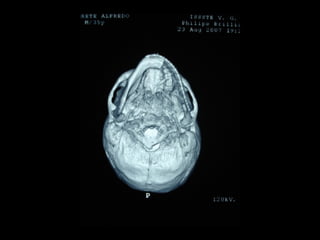

Tomografía computarizada

De seno maxilar corte sagital.

Area de implantación

Dentaria.

Material osteoconductor

para elevar el piso antral

Nuevo piso del seno y su

margen de seguridad para

contener el implante

Tomografía computarizada De senomaxilar corte sagital. Area de implantación Dentaria.